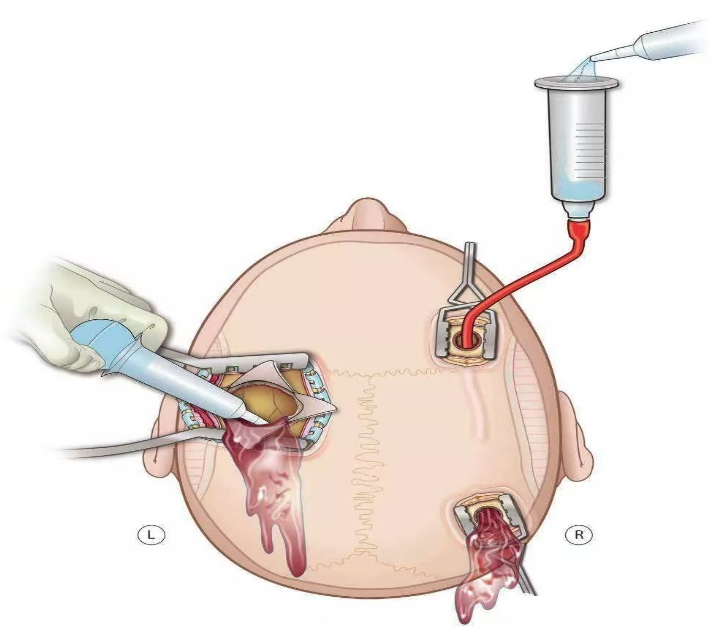

对许多老年人而言,一次轻微的头部磕碰,可能在未来几周或几个月里,悄悄引发一系列变化:走路不稳、手脚无力、记性变差,甚至性格改变,这背后,可能是一种名为“慢性硬膜下血肿”的疾病在悄然进展,它虽起病隐匿、发展缓慢,但会持续压迫大脑,影响正常功能。所幸,现代神经外科的微创手术为治疗此类疾病提供了新的选择,尤其为高龄或身体状况复杂的患者带来了新希望。 微创技术化解高龄手术难题 前不久,一名95岁的高龄患者因双腿无力、多次在家跌倒,并已无法像往常那样站立及行走,家人见状立即将老人送至贵州航天医院就医,通过影像检查发现颅内两侧都有慢性硬膜下血肿。追溯原因,竟是两个月前一次未加留意的头部轻微磕碰。 磁共振影像显示双侧颅内血肿 鉴于患者年事已高,且心肺功能不佳,神经外科团队经过细致评估,决定采用微创手术清除双侧颅内血肿。手术仅在头部开一个极小的创口,置入细软的引流管,将长期积聚的陈旧血液缓缓引出,解除大脑受压,整个过程约30分钟,创伤小,出血少。术后,患者恢复得很快,不久便能自己稳稳站立、独立行走,精神和食欲也好了很多。 疾病知识 慢性硬膜下血肿好发于大脑有一定萎缩的老年人,由于颅腔空间相对增大,头部即使受到很轻的撞击,也可能使大脑表面脆弱的静脉撕裂并缓慢渗血,血液逐渐积聚形成血肿,经过一段“潜伏期”后才压迫脑组织引起相关症状。 如果您或家中的长辈曾有头部外伤史(哪怕当时觉得不重),之后逐渐出现以下情况,请务必留心: ※一侧手臂或腿脚越来越没力气,走路易歪斜、跌倒。 ※反应比以前慢,记忆力明显减退,话变少或表达不清。 ※精神状态不佳,总想睡觉,或性格、情绪出现反常变化。 ※持续或反复的头痛、头晕。 注:本文仅为医疗技术介绍及健康科普知识分享,具体治疗方案请务必咨询临床医生,并结合患者个体情况制定。部分图片来源于网络,如有侵权,请联系删除。 贵州航天医院 神经外科专家简介 廖洪民 神经外科党支部书记、主任,主任医师 临床擅长:从事神经外科专业约30年,擅长脑部病变显微手术、立体定向手术等微创治疗。 贵州省医学会神经外科分会委员,遵义市医学会神经外科分会常务委员,遵义市中西医结合学会理事,中国生命关怀协会脑卒中救治及康复照护专业委员会委员,遵义市脑损伤评价医疗质量控制中心专家,遵义市劳动能力鉴定委员会医疗鉴定专家。 朱家伟 神经外科副主任医师 临床擅长:从事神经外科工作26年,擅长颅脑损伤救治及脑出血微创手术。 遵义市医学会神经外科分会委员、遵义市中西医结合学会脑心同治专业委员会常务委员。 黄建军 神经外科副主任医师 临床擅长:从事神经外科工作20年,对神经外科常见病、急危重症有丰富诊疗经验,熟练掌握神经外科微创手术。 贵州航天医院神经外科简介 • ✦ 基本情况 ✦ • 贵州航天医院神经外科于2008年独立建科,是首批国家卫健委能力建设和继续教育神经外科建设中心,贵州省神经外科介入联盟单位。现有专业技术人员17人,其中高级职称4人,中级5人,初级7人。 科室配备STORZ神经内镜系统、德国莱卡手术显微镜,国产西山开颅动力系统、蛇牌双极电凝、Mayfield头架等颅脑手术设备,以及无创和有创颅内压监护仪、正中神经刺激仪、脑循环康复治疗仪、排痰机、下肢康复训练器、气垫床、多参数监护仪等现代化医疗设备,为病区各种急、危、重患者的观察、监护和治疗保驾护航。 • ✦ 专科特色 ✦ • (一)脑出血微创手术治疗 应用范围:各种病因导致的自发性脑出血(高血压脑出血、脑淀粉样血管病相关脑出血、抗凝药物相关脑出血等)。 技术优势:微创、精准、恢复快。 (二)颅脑病变显微切除术 应用范围:颅内各种占位性病变(脑囊肿、脑肿瘤等)。 技术优势:精确度高、创伤小、恢复快。 (三)颅脑创伤综合救治 应用范围:各种类型的颅脑损伤、创伤性颅内血肿及颅脑创伤并发症、后遗症等。 技术优势:快速精准诊断、个体化手术与监护、早期康复干预,伤者病死率低、并发症少。